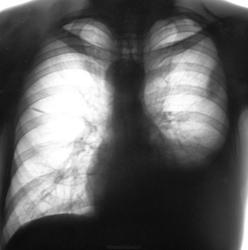

Через 8 месяцев пациент "простыл" и был направлен терапевтом на "флюшку" по поводу пневмонии, почему, именно, на флюорографию, ибо, состоит на учете у фтизиатра, совсем не понятно.

Коллеги, вместе с фтизиатром решили пролечить пневмонию в условиях отделения общего профиля.

Лечили интенсивно две недели. Итог лечения ниже.

Пацент направлен в облтуббольницу.